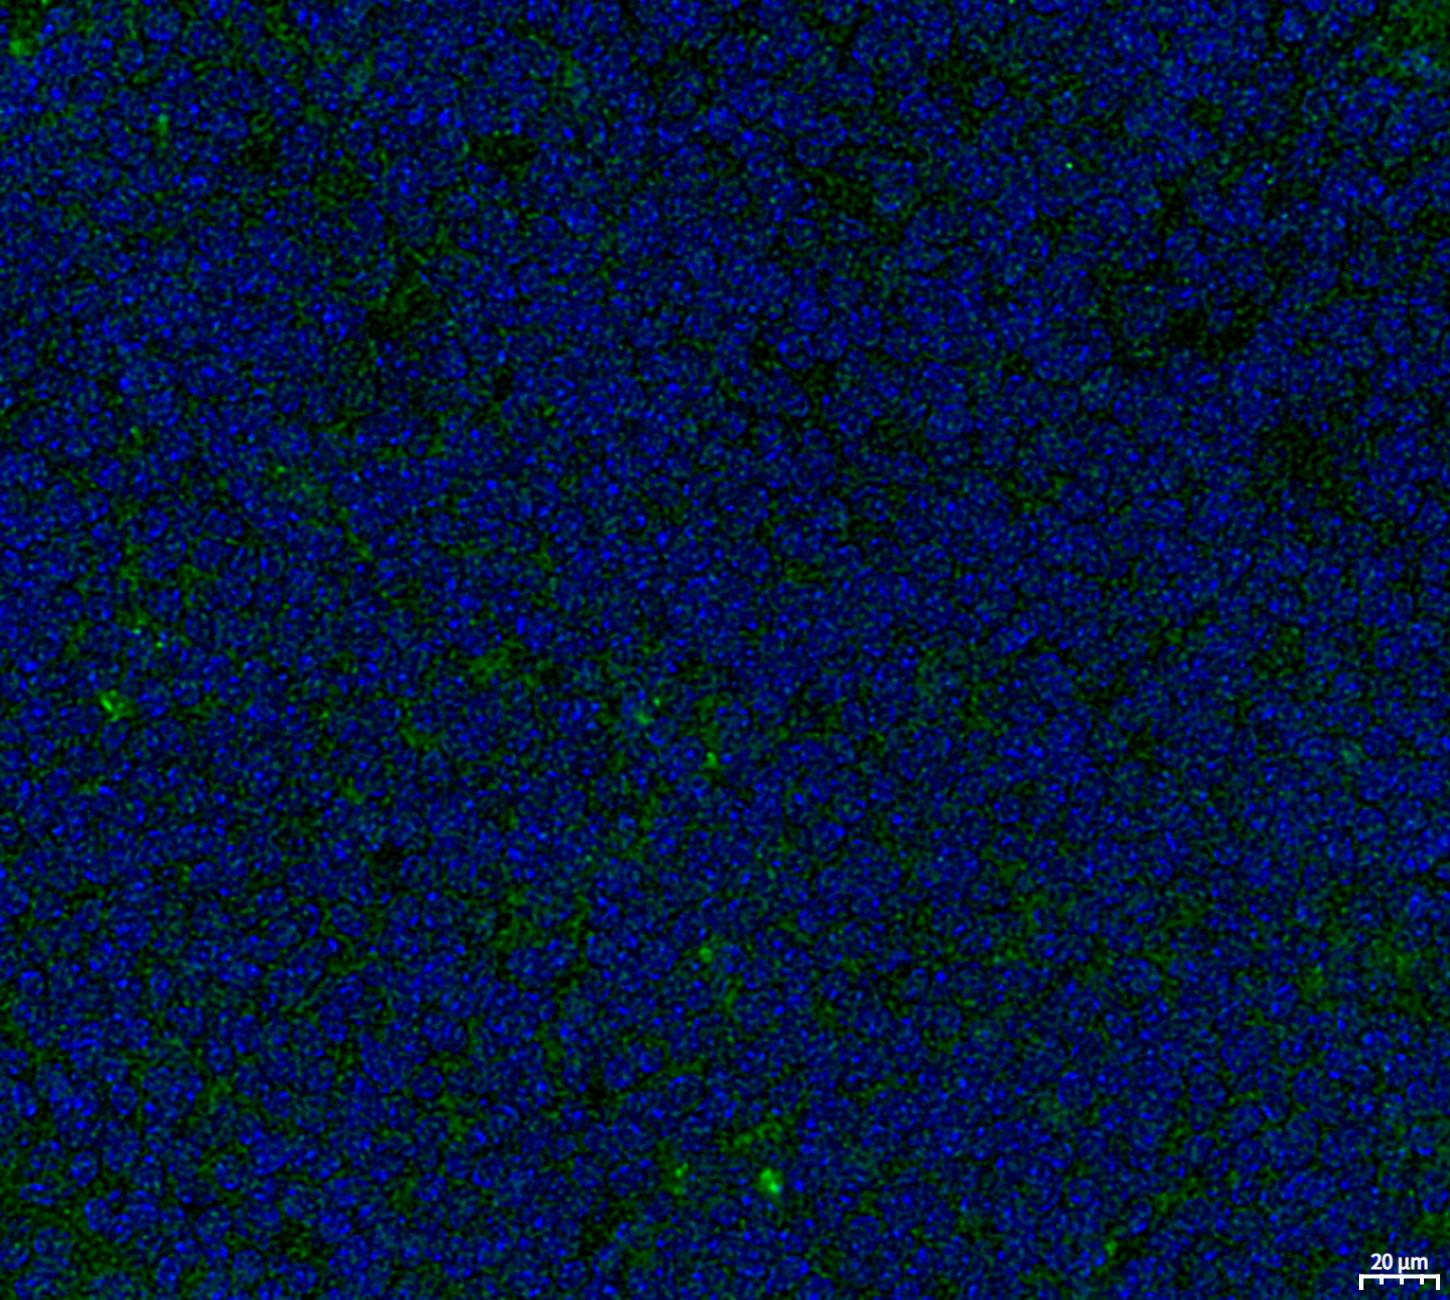

• Immunofluorescent analysis of Raji cells using F3757 (green, 1:250), Hoechst (blue) and tubulin (Red).